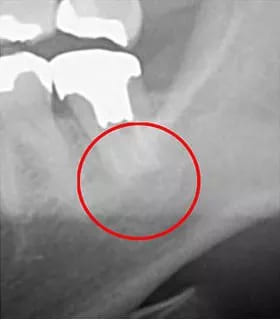

一般的なレントゲンは2次元(平面)の画像しか撮影できませんが、CT装置は顎の状態を3次元(立体)で撮影することができます。CT装置を使うことで診断の精度が大幅に向上し、レントゲンでは確認できなかった部分まで詳しく見ることができるのが大きな強みです。

以下は、CT画像とレントゲン画像です。このように、レントゲンだけでは病巣を見つけられなかった可能性があります。「見つからない=治療ができない」ということになり、それは根管治療の再発リスクが高まることを意味します。

CT画像

レントゲン画像